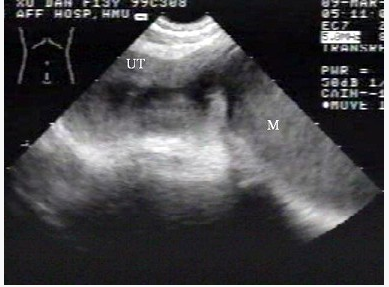

女性,62岁,1周前疑诊为宫颈癌。超声检查如图,最可能的诊断是()。